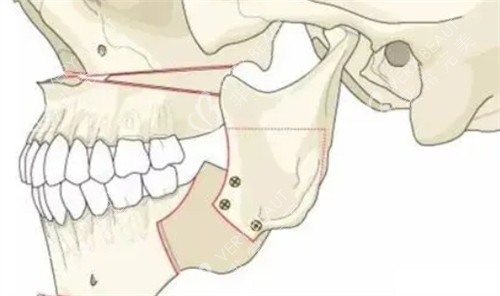

三、3D截骨技术:医生的“魔法刀”,我的“救命绳”

“我们用3D截骨技术,先模拟你的术后结果,再精细截骨。”手术前一天,医生拿着我的3D模型,边比划边说。我盯着那个“虚拟下巴”,心跳得像打鼓——这要是截歪了,我后半辈子怎么办?

后来才知道,3D截骨技术有多“神”:

精细定位:医生用3D扫描我的头骨,在电脑上模拟截骨路线,连0.1毫米的误差都要算清楚。

减少损伤:传统截骨靠医生经验,容易碰到神经;3D技术能避开血管和神经,术后肿胀轻一半。

结果可预:手术前就能看到术后侧脸,不像以前“盲做”,做完才发现“不是想要的”。

手术当天,我躺在手术台上,盯着房顶上的灯想:“要是截歪了,我就去当‘月亮脸’博主。”结果4小时后醒来,下巴缠着绷带,疼得直抽抽,但摸到平整的下巴线,突然觉得“值了”。

3D截骨技术真的“神”吗?

——对医生来说,是更精细的工具;对我来说,是“不用赌运气”的安心,是“术后不用哭”的底气。